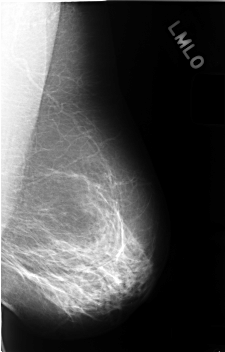

C_0404_1.LEFT_MLO

LEFT_MLO LINES 4576 PIXELS_PER_LINE 2920 BITS_PER_PIXEL 12 RESOLUTION 50 NON_OVERLAY